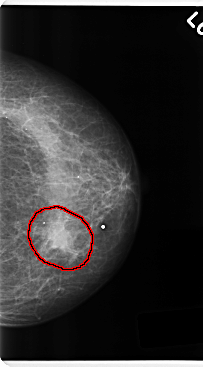

C_0216_1.LEFT_MLO

LEFT_MLO LINES 4744 PIXELS_PER_LINE 2624 BITS_PER_PIXEL 12 RESOLUTION 50 OVERLAY

FILE: C_0216_1.LEFT_MLO.OVERLAY

TOTAL_ABNORMALITIES 1

ABNORMALITY 1

LESION_TYPE MASS SHAPE IRREGULAR MARGINS ILL_DEFINED

ASSESSMENT 4

SUBTLETY 5

PATHOLOGY MALIGNANT

TOTAL_OUTLINES 1

BOUNDARY